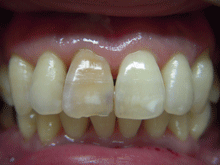

オールセラミックス

金属を使わずに全てセラミックを使用し、光の透過性を上げる事により自然な白い歯に回復させる方法です。

現在では土台から白い材質(ファイバーポストなど)の物を使用することにより、さらに透明感が増し天然歯に近似しています。

オールセラミックは近年進化を遂げており、強度や接着性がかなり改善され、審美的にとても優れたものと成って来ております。

オールセラミックにも色んな種類がありますが、当院ではe-max(二ケイ酸リチウムガラスセラミック、)ジルコニアセラミックスを採用しています。